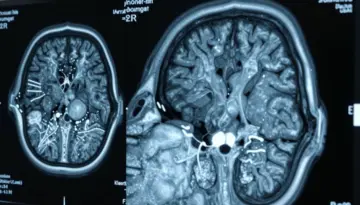

قام باحثون من تحالف ميديكال، وهو مزود رائد لخدمات التصوير في أوروبا، بمراجعة فحوصات PET-CT المرتبطة بالسرطان لمرضى يتناولون أدوية GLP-1. تتضمن فحوصات PET-CT حقن كمية صغيرة من السكر المشع في مجرى الدم؛ تمتص خلايا السرطان، بنشاطها الأيضي الأعلى، كمية أكبر من هذا المتتبع. عند فحصها، تساعد هذه النقاط الساخنة الأطباء في تحديد الأنسجة غير الطبيعية.

ومع ذلك، وجدت الدراسة أن المرضى الذين يتناولون أدوية GLP-1 غالباً ما يظهرون أنماطاً غير معتادة في الفحوصات. يمكن بسهولة أن يُخْطَأ في تفسير هذه الشذوذات على أنها مرض، خاصة إذا لم يكن الأطباء على علم بأن المريض يتناول هذا النوع من الأدوية. وقد يؤدي التفسير غير الدقيق لهذه النتائج إلى اختبارات لا ضرورة لها، أو تصنيف غير صحيح للسرطان، أو حتى تأخير العلاج.